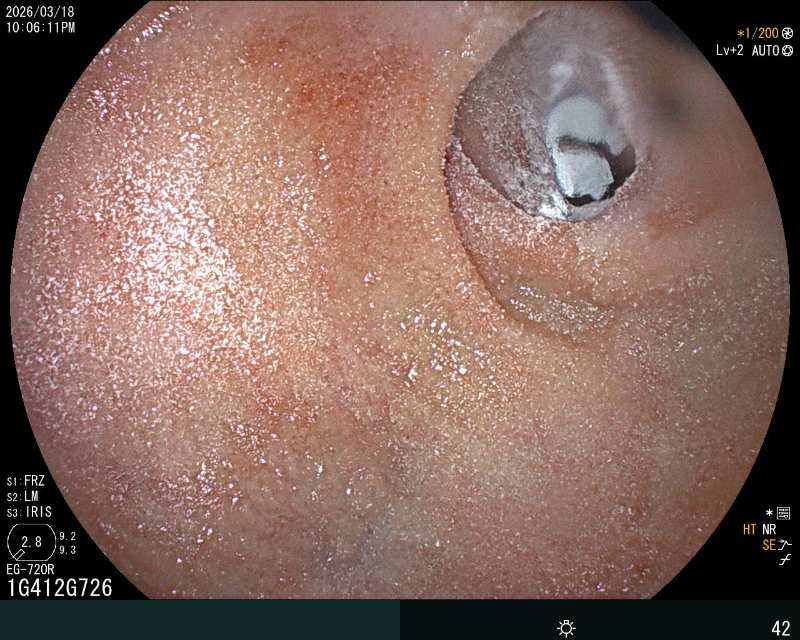

十二指肠球球部喷洒止血粉

在重症医学科(ICU)团队严密监护保障下,消化科内镜团队克服患者休克、体位受限等困难,紧急开展床旁急诊胃镜。镜下可见出血病灶位于十二指肠球部出现糜烂渗血,一处8×4mm 深溃疡覆血痂及污苔,活动性渗血明显,且黏膜严重水肿、肠腔狭窄,内镜镜身不能通过,操作难度极大。内镜团队通过精准操作,利用去甲肾上腺素联合冰盐水反复冲洗创面,收缩血管减少出血,再通过内镜通道将止血粉均匀喷洒于糜烂及溃疡面。药物覆盖后,渗血即刻停止,创面形成稳定保护层,成功止血。次日胃镜复查显示,患者溃疡创面已覆盖厚白苔,活动性渗血完全消失,黏膜水肿显著消退,肠腔狭窄改善,止血效果确切,为后续抗感染、纠正休克等综合治疗赢得关键时间。目前患者生命体征平稳,未再出现消化道出血。